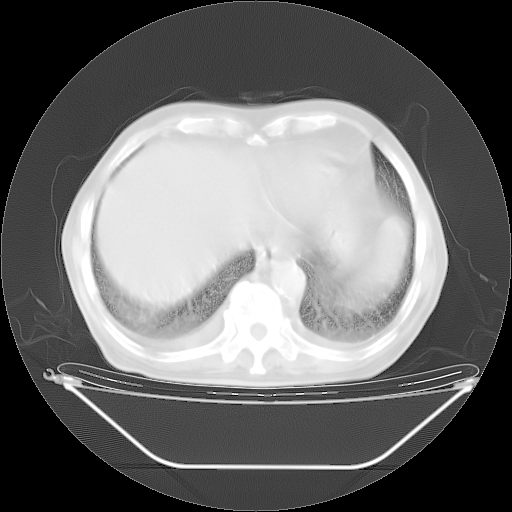

今天复查肺部CT,发现双肺广泛磨玻璃样改变。所以我把3月19日和5月9日相隔50天的肺部CT上传。请大家会诊。

5月9日肺部CT(在4月27日齐鲁医院肺部CT描述部分肺组织磨玻璃样改变,12天后肺组织广泛磨玻璃样改变)

2009年5月9日肺部CT

大致读了系列胸部CT:纵隔窗无明显异常,肺窗:从4、27至今:主要是双肺中下野外带可见毛玻璃样改变,目前处于急性肺泡炎阶段,至于原因考虑1、结替组织或胶原血管性疾病所致?2、恶性疾病如恶组在肺部所致的表现或细支气管肺泡癌?3、药物或其它原因如肺蛋白沉着症所致肺泡炎目前不太可能?总之,明天就去请我院的呼吸科、感染科、血液科和临免专家会诊哈。